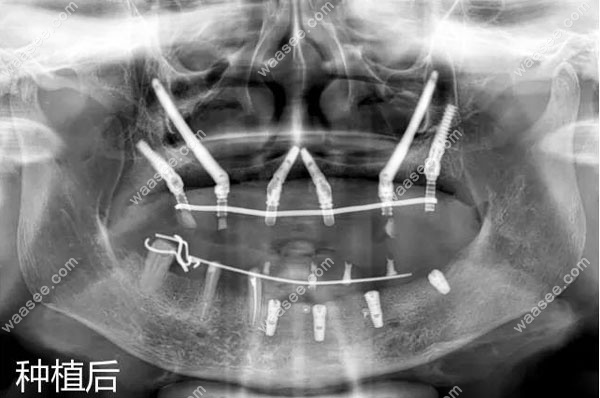

穿颧穿翼种植后的全景片效果

穿颧穿翼种植的原理,就是利用穿颧种植体一端穿过颧骨,另一端平台放置在接近牙槽嵴顶的位置,让种植体有一个45°的转角基台,这样一来,获得的咬合力主要由颧骨支持。

所以,对于颌骨重度缺失的情况,不用植骨也可以进行种植修复。

同时,利用后牙区上颌结节及翼板,固定远端两颗植体,让上半口牙的稳固度及承重能力得到倍增。